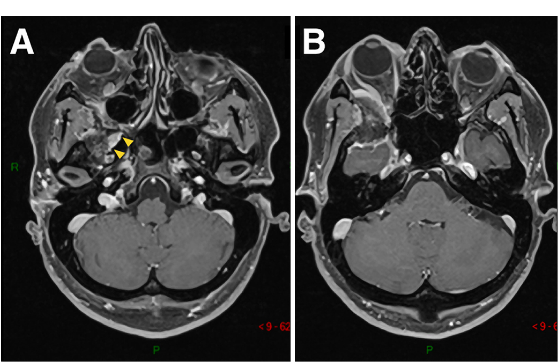

41歲男性,蝶眶腦膜瘤繼發(fā)眼球突出,并延伸至前床突和蝶竇(SphS)。

圖1A-D:術(shù)前MR顯示蝶眶區(qū)腦膜瘤占位,增強(qiáng)病灶,浸潤(rùn)延伸至蝶腭窩(黃色箭頭)。

▼術(shù)后影像復(fù)查:證實(shí)腫瘤被完全切除。E-H:術(shù)后軸位MR圖像顯示腫瘤完全切除。

術(shù)后影像復(fù)查:證實(shí)腫瘤被完全切除。E-H:術(shù)后軸位MR圖像顯示腫瘤完全切除。